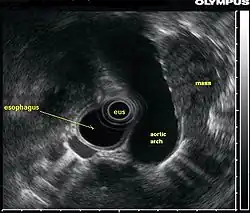

L’échographie endoscopique (EUS, acronyme de l'anglais Endoscopic ultrasound), appelée aussi ultrason endoscopique ou écho-endoscopie, est un acte médical qui emploie une source d’ultrasons au bout d’un endoscope relié à un échographe pour obtenir des images des organes internes de la poitrine et de l'abdomen. Elle peut être utilisée pour visualiser la paroi de ces organes ou pour examiner les structures adjacentes. Combiné avec l'échographie Doppler, le flux des vaisseaux sanguins avoisinants peut également être analysé.

La qualité de l'image produite est directement proportionnelle à la fréquence utilisée. Par conséquent, une haute fréquence produit une meilleure image. Cependant, l'échographie à haute fréquence ne pénètre pas aussi bien que les ultrasons basse fréquence de telle sorte que l'examen des organes voisins peut être plus difficile. L'écho endoscopie s'effectue sous anesthésie générale.